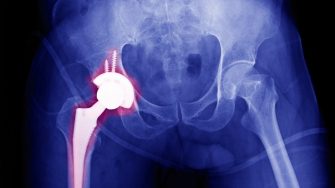

You will design, develop, manufacture and evaluate new medical implants with excellent robustness and multifunctionality using cutting-edge metal/polymer 3D printing.

This project has the potential to benefit millions of patients worldwide. It will fill a critical knowledge gap in the medical implant field by developing new topology-optimised designs and 3D printing processes to promote bone in-growth.

• Designing new bioactive and multifunctional (e.g., antibacterial) biomaterials to 3D print medical implants

• Modifying the surfaces of 3D printed lattice structures to enhance (osseointegration) bone ingrowth/ ongrowth.

• Characterising the microstructure, bio (in vitro or in vivo) and mechanical properties of your 3D printed parts, then benchmarking them against similar products already available on the market

• Medical devices (Orthopaedics/Spine)